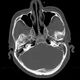

Qua thăm khám và kết quả cận lâm sàng phát hiện tình trạng tăng áp lực nội sọ và liệt mặt do khối u lớn vùng góc cầu tiểu não bên phải chèn ép các dây thần kinh gây giãn não thất phía trên.

Kết quả chụp cộng hưởng từ kiểm tra cho thấy tình trạng giãn não thất cải thiện rõ rệt sau mổ, điều này có nghĩa là tăng áp lực nội sọ là do chính bản thân khối u phát triển kích thước quá lớn.

Cân nhắc tuổi thai lúc này đã được 32 tuần và nguy cơ khối u chèn ép gây tụt kẹt não, các bác sĩ đã hội chẩn liên chuyên khoa và đưa ra chỉ định mổ lấy thai chủ động rồi mổ lấy u não sau đó 2 ngày.